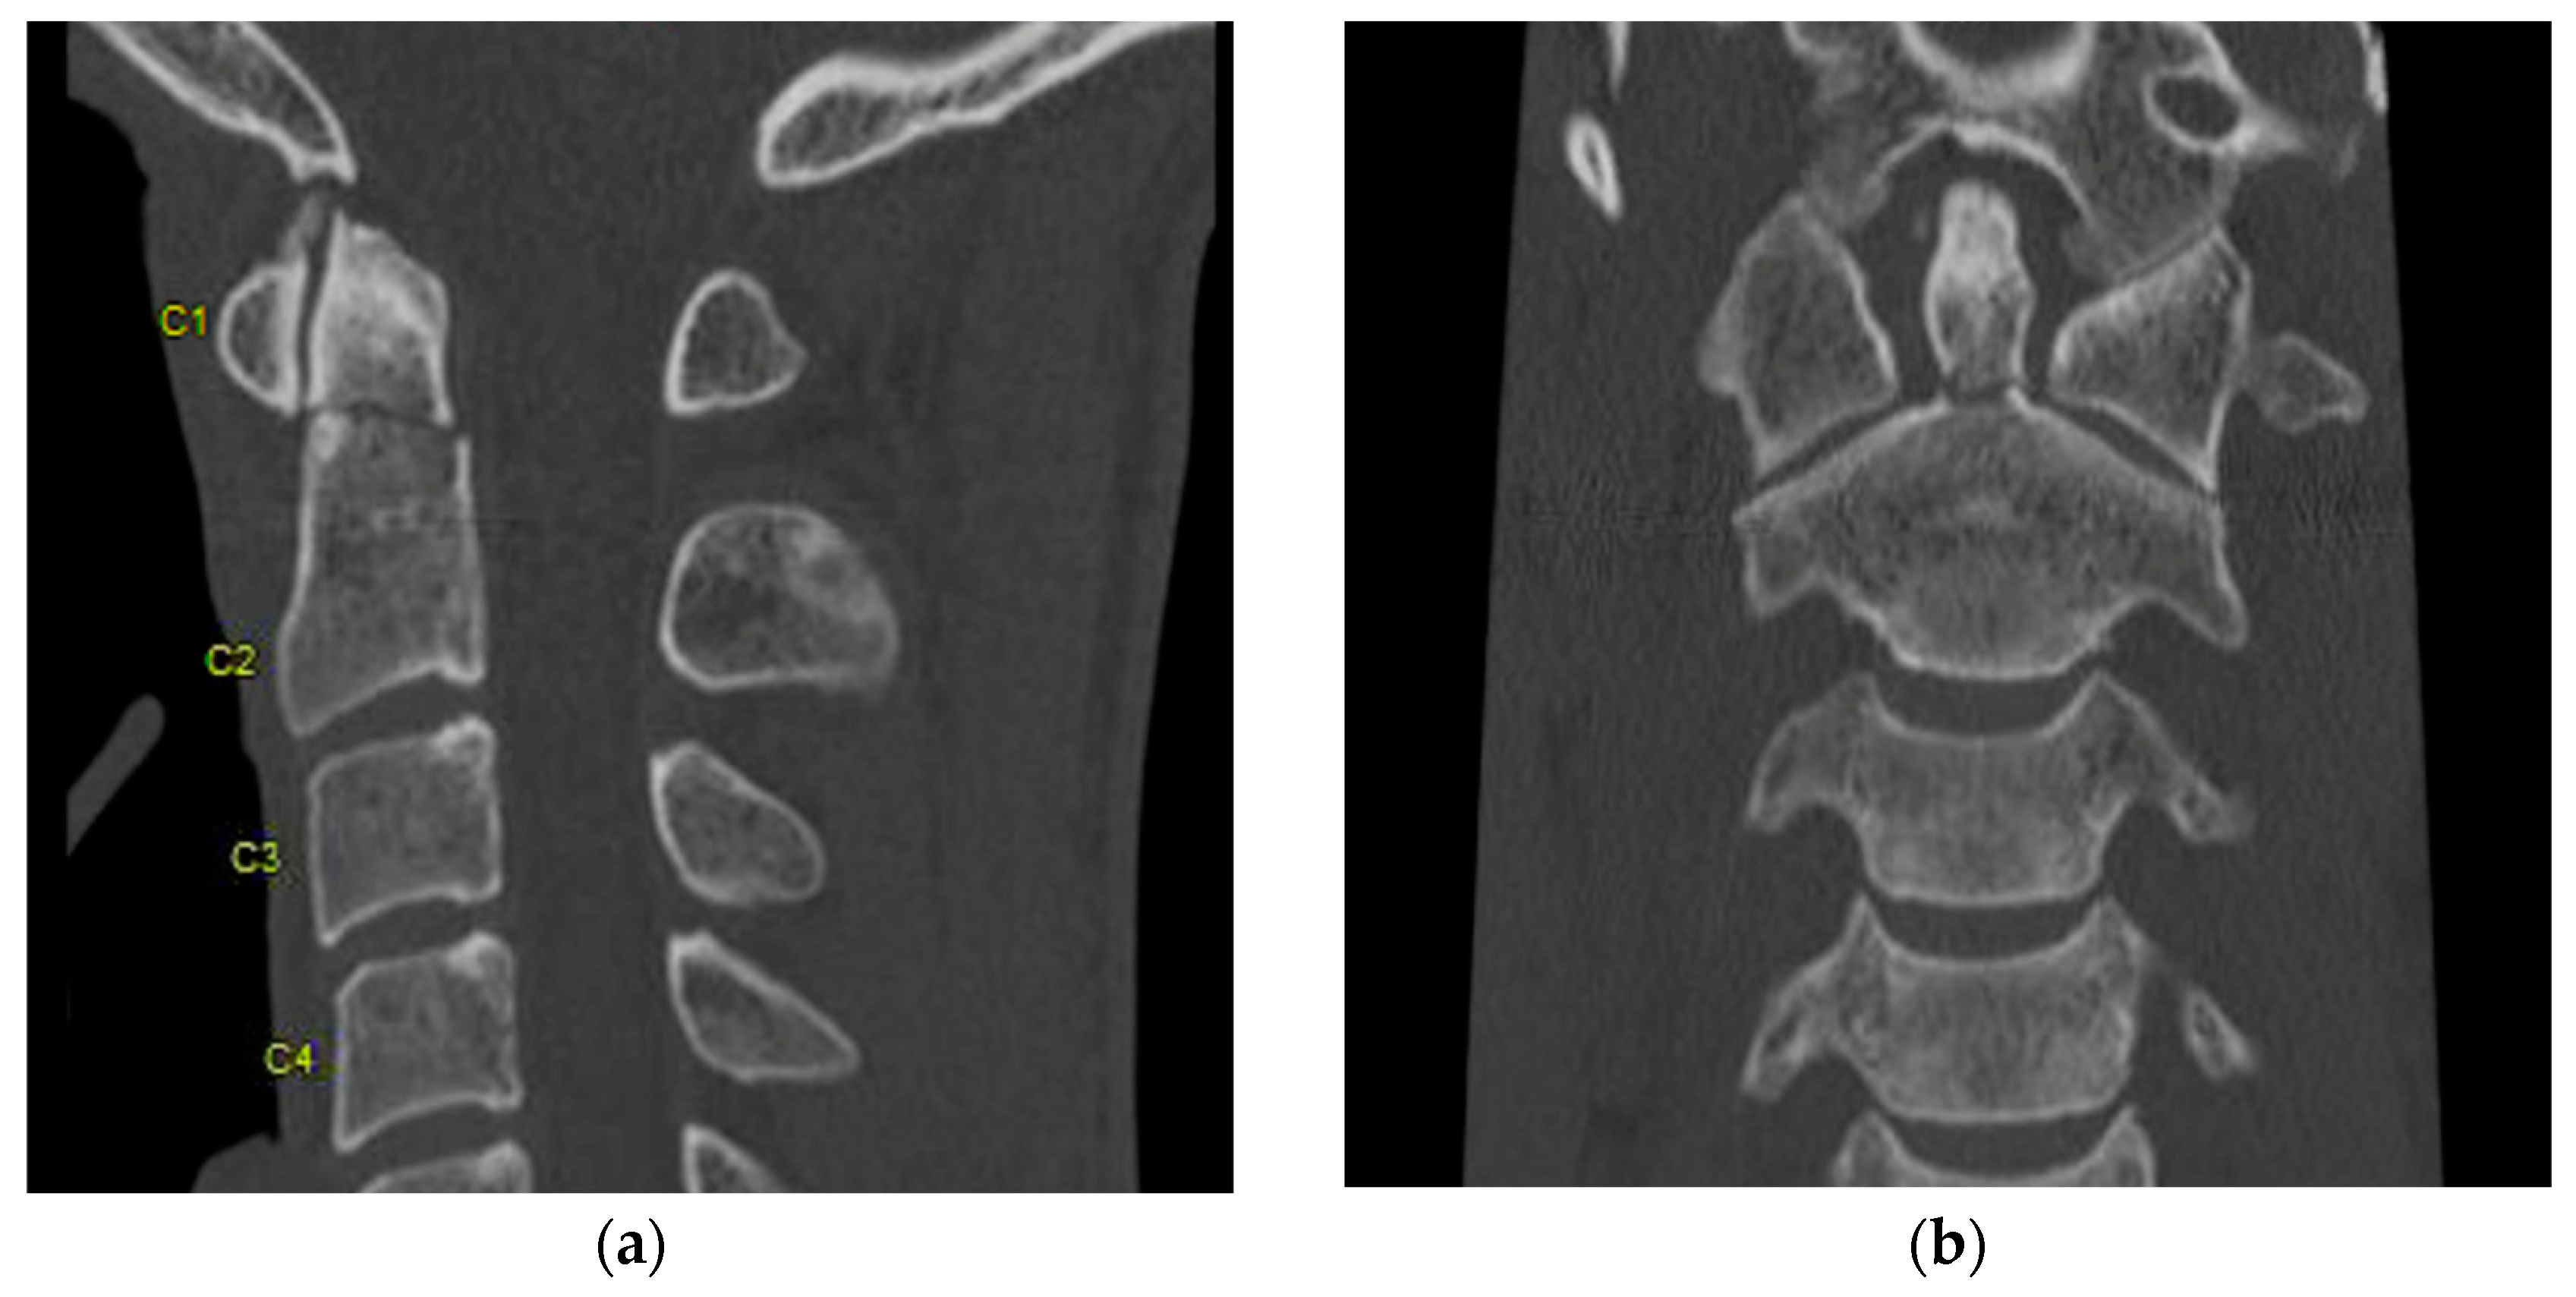

The American College of Radiology recommends CT as the initial imaging modality for the evaluation of spinal trauma in adults and children older than 14 years [6]. CT provides great detail regarding osseous anatomy and its associated pathology (Figure 1 and Figure 2) but can also reveal significant abnormalities such as traumatic disk herniations and epidural or subdural hematomas in the spinal canal.

Figure 1.

(a) Sagittal and (b) axial view of CT showing L3 burst fracture with significant retropulsion of the vertebral body into the spinal canal and loss of body heigh. There is involvement of the posterior elements.

Figure 2.

(a) Sagittal and (b) coronal view of CT showing type II dens fracture. “C1–C4” Designate each corresponding spinal level.